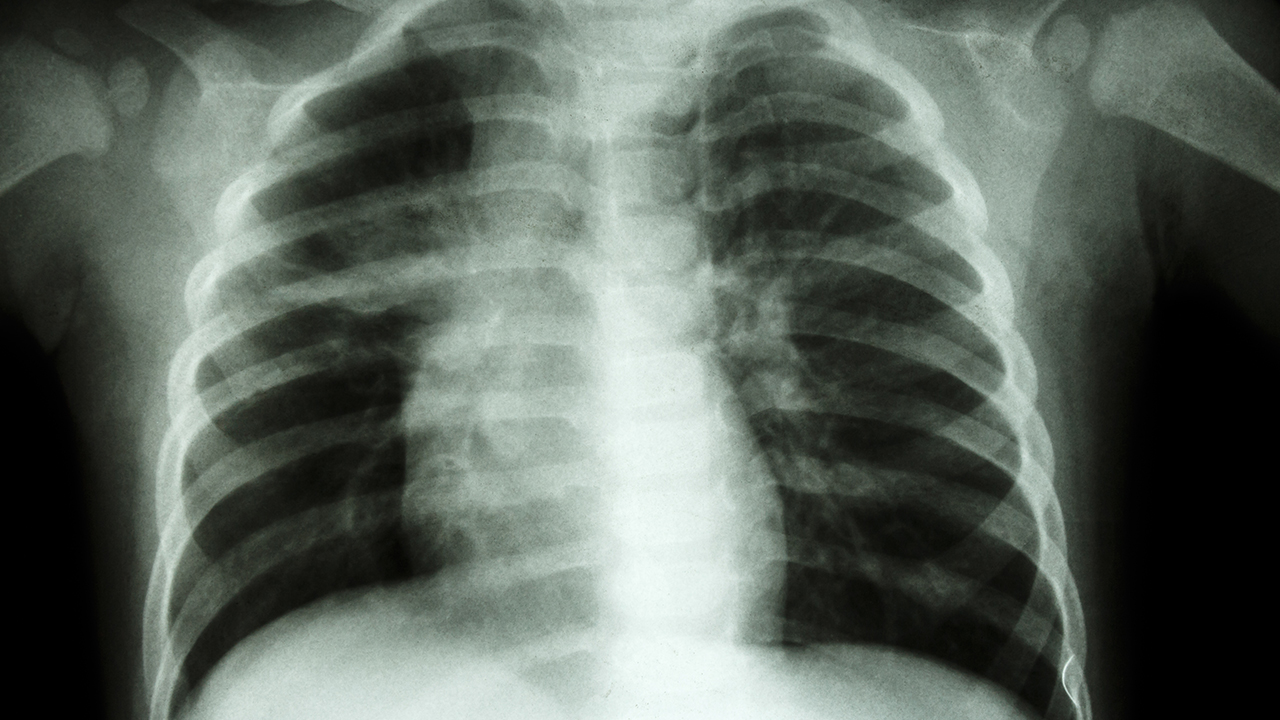

肺癌的发病原因复杂,包括吸烟、空气污染、职业暴露、遗传因素等。早期诊断和规范治疗对提高患者生存率至关重要。目前肺癌的治疗方法主要包括手术、放疗、化疗、靶向治疗和免疫治疗等。